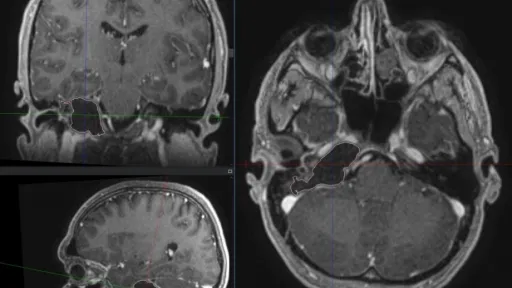

În premieră, medicii specialiști neurochirurgi de la Institutul de Medicină Urgentă au operat cu succes o tumoră de bază craniană profundă. Pacientul chiar din prima zi postoperator a reușit să se deplaseze și nu a prezentat deficit neurologic adițional. A fost externat din spital după cinci zile de la intervenție.

Pacientul care a fost operat este un bărbat de 40 de ani, diagnosticat cu tumoră gigantă de bază craniană profundă cu extindere în apexul petros, urechea internă și fosa posterioară.

Pacientul a fost supus intervenției neurochirurgicale în Departamentul de Neurochirurgie din cadrul IMSP Institutului de Medicină Urgentă de înlăturare în totalitate a tumorii. Intervenția a fost posibilă atât datorată experienței echipei neurochirurgicale și neuro-anesteziei cât și tehnicii folosite intraoperatorii (microscop performant, drill cu viteză înaltă, neuronavigație). Durata intervenției a fost de patru ore.